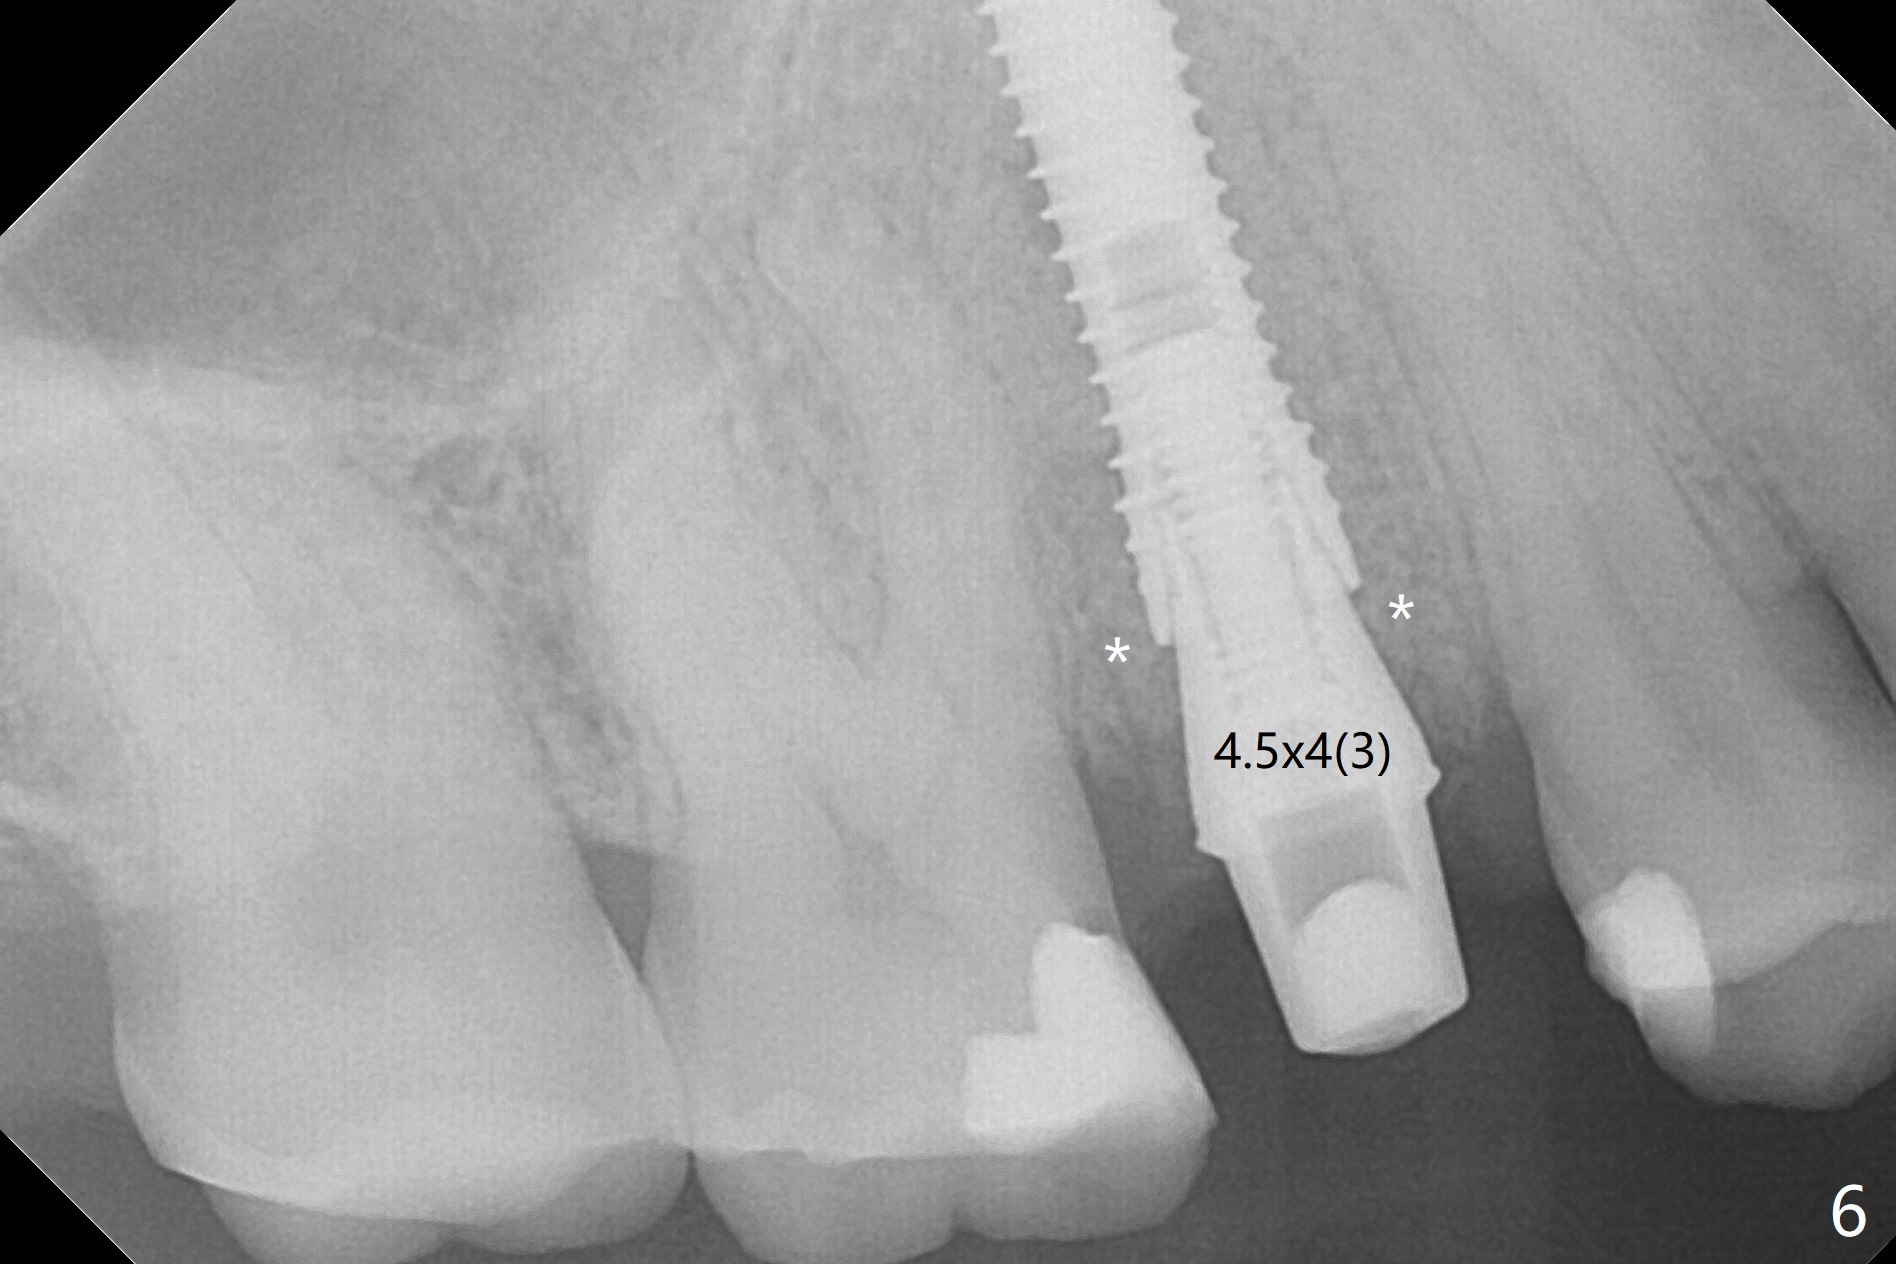

When the tooth #4 with vertical root fracture (Fig.1) is extracted, the buccal plate is found to be lost. The lowest point of the defect is shown as black dashed line in Fig.2 (yellow dashed line: sinus floor). After use of 2.5 mm reamer for 21 mm (buccal gingival level) and 3.0 mm reamer for ~17 mm, a 3.8x15 mm dummy implant is placed with 30 Ncm and 1.85 mm apical space (Fig.3 pink outline). A 3.8x18 mm (definitive) implant is placed with <40 Ncm with the implant plateau apical to the lingual crest (Fig.4,5). The buccal plate defect is repaired by Vanilla Graft (Fig.6 *) before and after insertion of a 4.5x4(3) mm abutment. The buccal plate defect seems to being repaired 4 months postop (Fig.7). Occlusal wear suggests bruxism, which is also associated with the root fracture. Night guard is recommended. The defect repair is close to completion 8 months post cementation (Fig.8). The crown/abutment is found to be loose 1 year 4 months post cementation and retightened without checking whether there is clinical 2nd DO caries of #3 (Fig.9, "sensitive to water pik"). A few days later, DO composite is being removed. It is difficult to determine whether the 2nd DO caries or gap has been removed with the neighboring crown in place. When the crown/abutment is removed and gingival retractions are inserted, there is no decay. The gap is removed. With Toflemire in place, the crown/abutment is reseated and hand tightened; after packable composite, the crown/abutment is removed, there is no more DO gap.

In fact there is a small buccal fistula, which is communicated with the underlying implant threads. Although preop CT shows that the buccal crest is lower than the palatal (3.8x13 mm, Fig.10 P) one, intraop finding of missing buccal plate should dictate a shorter implant (Fig.11) or onlay graft to avoid periimplantitis. Regeneration of the bone plate is limited. Later the fistula disappears with formation of a concavity (Fig.13). There is no symptom. Is bone graft necessary with a remote incision? 3-D images of CT taken 1 year 5 months post cementation show possible mesiobuccal and distopalatal bony defects (Fig.13-16). It is possible that bone graft was placed enough palatal (Fig.16). DO composite at #3 is redo satisfactorily (Fig.17 *).